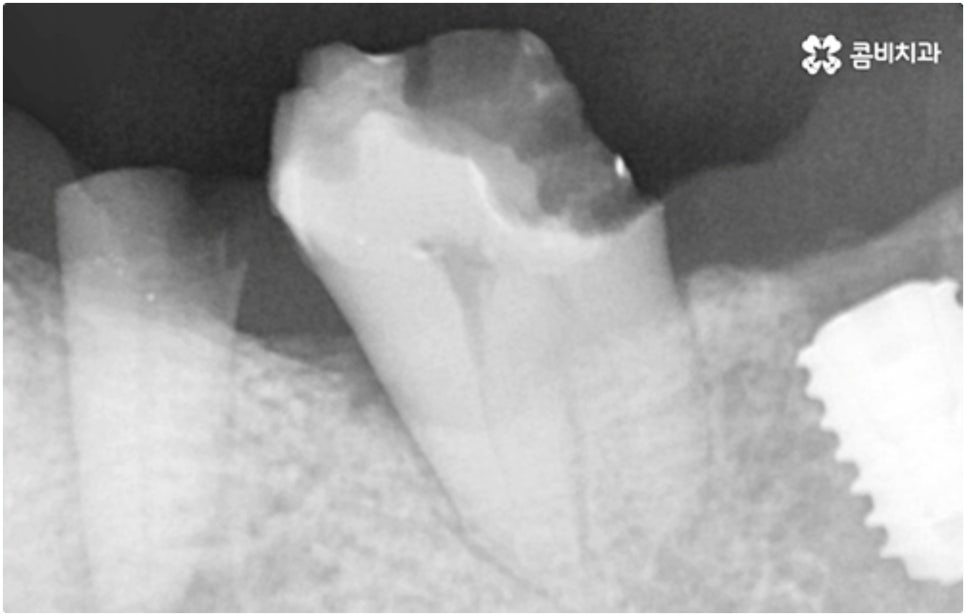

모든 치아가 위치와 모양이 제각각 다른데 특히 어금니는 구강 내 깊은 곳에 있고 주름진 저작면을 가지고 있기 때문에 관리할 때 더욱 주의할 필요가 있습니다. 꼼꼼하게 칫솔질을 해준다고 해도 음식물 찌꺼기가 남게 될 가능성이 높아 충치나 치주염 등 구강 질환이 빈번하게 발생할 수 있기 때문인데요, 이때 빠른 발견으로 초기 대처를 해주지 못하면 내부 신경까지 손상이 깊어져 치아를 발치하고 어금니임플란트 시술을 받아야 할 상황까지 발생할 수 있어요.

구강 질환 때문이 아니더라도 저작 기능의 핵심적인 역할을 담당하고 있어서 외부 충격 (실수로 딱딱한 것을 씹는 일 등) 에 노출될 위험도 큰데요, 만약 부러지고 금이 갈 때 뿌리까지 갈라졌다면 해당 어금니는 살릴 수 없고 인공 치아로 대체해야 할 거예요.

임플란트 시술이 환자분들의 잇몸뼈에 직접 고정을 시키는 방법인 만큼 개개인의 치주 상태, 구강 내부 구조 등을 면밀하게 살펴보고 치료 계획을 세워야 하며 그 밖에도 치아가 빠진 지 얼마의 시간이 흘렀는지, 장기적으로 복용 중인 약이 있는지 등 영향을 줄 수 있는 모든 관련 상황을 종합적으로 고려하여 환자분들에게 딱 맞는 어금니임플란트 시술을 무리하지 않게 진행하는 것이 중요한 체크 포인트라고 할 수 있는데요. 그렇기 때문에 먼저 3D CT를 이용한 정밀한 검사를 통해 어떤 종류의 임플란트를 어떻게 진행할지 신중하게 검토해야 하며 또한 풍부한 노하우와 뛰어난 기술력을 갖추고 있는 의료진과 함께 충분한 사전 상담을 하실 필요가 있습니다.

식립 성공률 및 지속적인 안정성을 높이기 위해서는 초기 고정이 잘 이루어져야 하는데 만약에 식립 바탕이 되는 잇몸뼈의 상황이 좋지 않다면 이와 관련된 치료를 먼저 해 줘야 하는 거예요. 예를 들어 치주 질환이 심하다면 이를 깨끗하게 치료해 주는 것이 우선시 되어야 하고, 잇몸뼈의 높이나 밀도 등이 부족한 경우에는 뼈이식 과정을 통해 이를 먼저 보충해 줄 필요가 있어요. 또한 윗어금니가 빠진지 오랜 시간이 지나 이미 골흡수가 일어나고 상악동이 많이 내려와 있다면 상악동 거상술 및 뼈이식을 한 후 임플란트 식립을 진행해야 할 거예요.